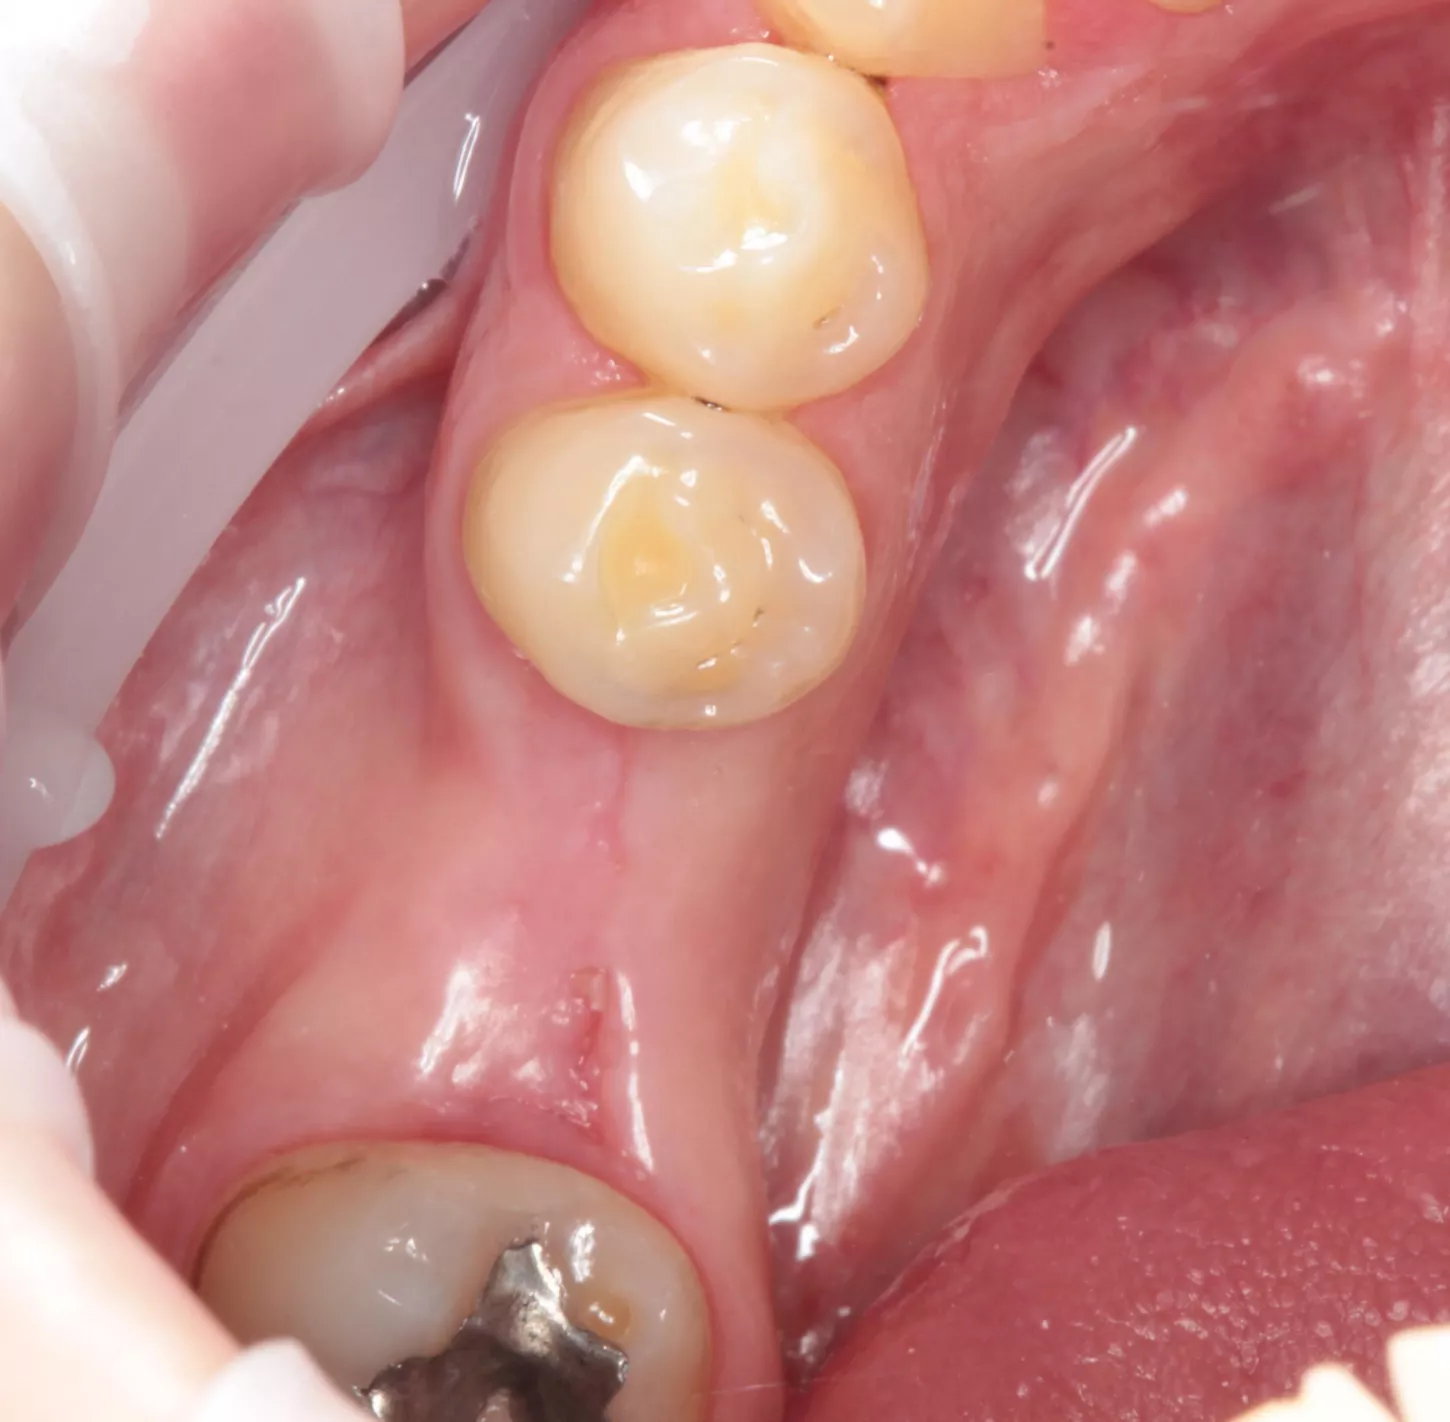

15a. 15b. La restauration finale a été mise en place dans la bouche du patient 2 semaines plus tard. Le patient et moi-même sommes satisfaits du résultat.